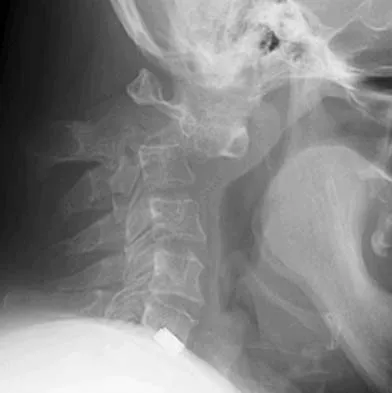

Figures 5a and 5b show the radiograph and MRI scan of a patient who has severe mechanical neck pain but no neurologic problems. Biopsy and work-up show the lesion to be a solitary plasmacytoma. Treatment should consist of

Explanation

Plasmacytoma is very sensitive to radiation therapy and given the complexity of the resection and complications of surgery in the given location, radiation therapy is preferred. However, the patient has clear loss of bony structural integrity, and resultant instability would persist even with tumor irradiation; therefore, posterior stabilization is warranted. Chemotherapy and bone marrow transplant are reserved for systemic disease with multiple myeloma. Corwin J, Lindberg RD: Solitary plasmacytoma of bone vs. extramedullary plasmacytoma and their relationship to multiple myeloma. Cancer 1979;43:1007-1013.